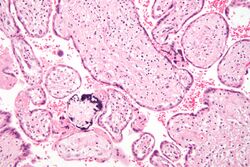

Micrograph of cytomegalovirus (CMV) infection of the placenta (CMV placentitis), a vertically transmitted infection: The characteristic large nucleus of a CMV-infected cell is seen off-centre at the bottom right of the image, H&E stain.

Apart from infecting the fetus, transplacental pathogens may cause placentitis (inflammation of the placenta) and/or chorioamnionitis (inflammation of the fetal membranes).[citation needed]

CMV placentitis